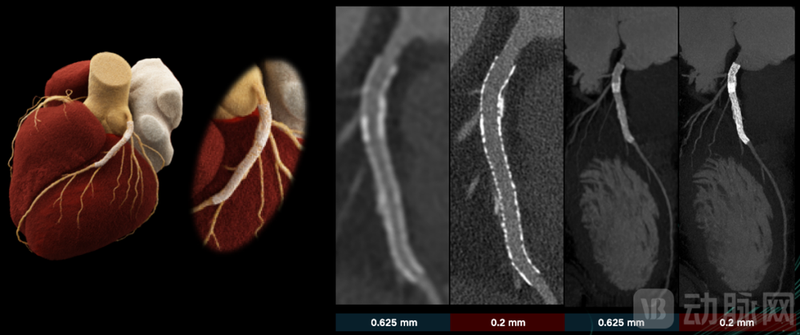

CMEF期间,东软医疗正式对外披露详细披露了NeuViz P10的参数及优势。东软医疗首席执行官武少杰在发布会上介绍:NeuViz P10搭载了新一代碲锌镉光子计数探测器实现零噪声光子计数 CT成像,空间分辨率超越46.5lp/cm。

此外,该光子计数CT还拥有光子超音速特性,转速突破了0.23s大关。结合第三代冠脉运动伪影校正技术,NeuViz P10可为超高清冠脉成像提供了坚实的保障。在检查冠状动脉时,支架、钙化、斑块等成像显示更清晰。

联影医疗目前CdTE、CZT都有布局,但本次CMEF没有透露展出的uCTUltima具体使用了哪一条路径。但有透露:联影医疗在超清成像模式(UHR)方面取得了显著成果;除了在常规临床检查中表现出色外,联影医疗还成功突破了现有PCCT在超清成像模式中的数据传输限制,实现了更大的扫描覆盖范围,为心脏疾病的精准诊断提供了全新可能。